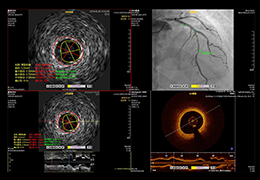

View X-Ray CT & MRI Scans Fast and Easily

Designed for surgeons, Pro Surgical 3D makes it easy to view patient scans quickly. Pro Surgical 3D facilitates the optimal 3D treatment and assessment workflows based on X-ray CT and MRI scans – and best of all, it’s FREE!

Traditional multi-planar slicing

High-quality and fast 3D reconstruction and 3D rendering

Multi-planar slicing.

Side-by-side comparative assessment for pre- and post-operative scans.